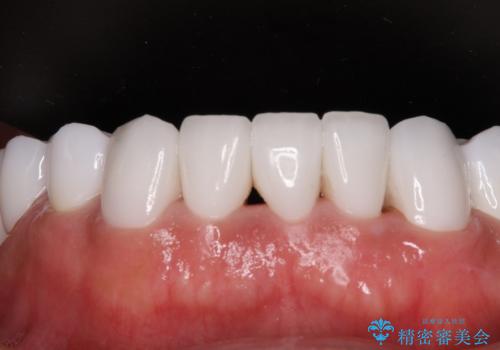

欠損と虫歯だらけの口の中 真っ白なセラミック治療

インプラントにより奥歯の咬み合わせが安定し、上顎前歯の歯肉ラインを調整するための骨外科処置により深く咬みこんでいた前歯部も負担のかからない咬み合わせに改善することができました。

治療終了直前に転勤となってしまい、最後2回の来院は新幹線にて来院いただくことになってしまいましたが、短期間で無事に終了することができました。